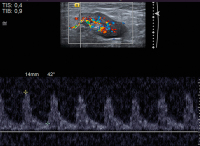

Lymphknoten-Ultraschall

Abbildung 4: PW-Doppler-Analyse. In der Literatur sind immer wieder Hinweise auf die Wichtigkeit der Analyse der Flusskurven intranodaler Arterien zu finden. Die relevanten Schwellenwerte für Resistance Index (RI) oder Pulsatilitätsindex (PI) schwanken in der Literatur stark. Prinzipiell sei bei pathologischen Lymphknoten mit einem eher hohen peripheren Widerstand mit entsprechenden RI und PI zu rechnen. An dieser Stelle seien dem geneigten Leser freie Gedanken zur zeitlichen Durchführbarkeit von Flussmessungen gegebenenfalls mehrerer Lymphknotenarterien mehrerer Lymphknoten mit den passenden Geräteeinstellungen innerhalb der täglichen Routine selbst überlassen. Lymphom.